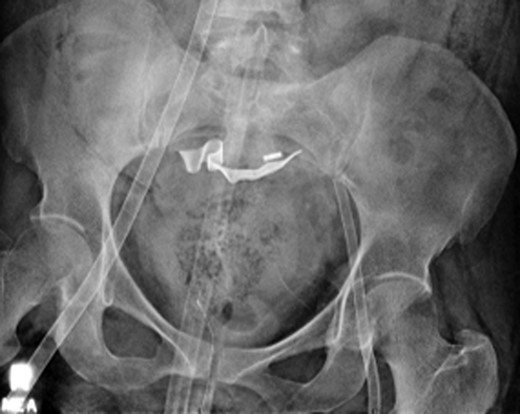

Once stable, imaging confirmed PE (Fig. 2) with a RV to left ventricle (LV) ratio of 2.1 (Fig. 3). The patient was then admitted to the ICU requiring inotropic support. Approximately 4 h later, the patient had concerning features of abdominal compartmental syndrome with increase abdominal distention and bladder pressures >25 mmHg was noted. Repeat imaging showed large volume hemoperitoneum emanating from the left hepatic lobe (Fig. 4). The patient underwent a decompressive laparotomy with a non-anatomic liver resection of segments I and II and temporary abdominal closure. Due to concerns of distal limb ischemia of the arterial cannulation site, an 8-Fr reperfusion cannula was placed in the left superficial femoral artery (SFA).

CTA abdomen performed when the patient had abdominal compartmental syndrome requiring massive transfusion protocol. CTA showing extensive hemoperitoneum with active extravasation from the left lobe of the liver.